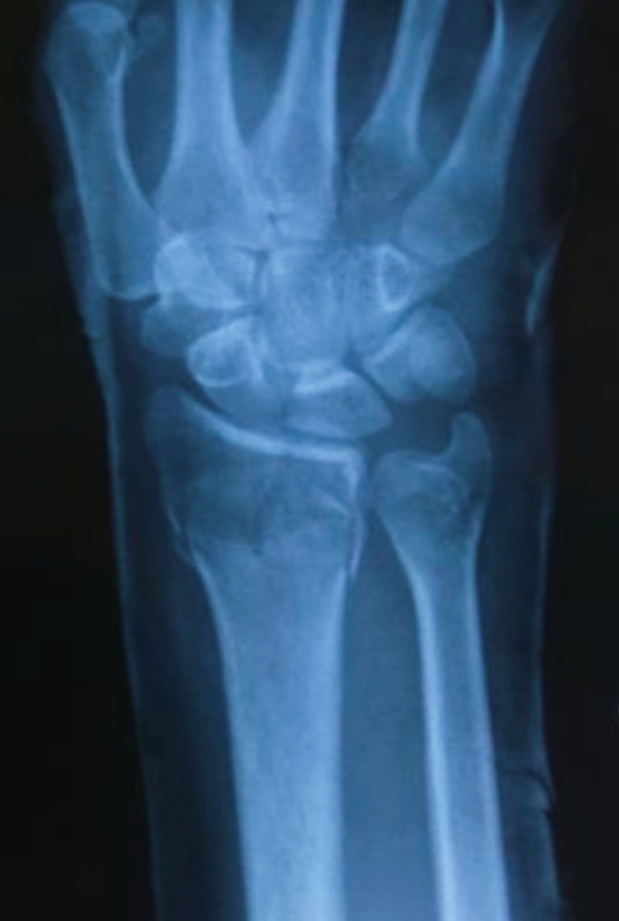

Как раз женщина и зашла. Назначен снимок лучезапястного и легких.

–А как же? Это все гололед, подкинул нам работы, мест почти нет.Вы же тоже наверное его жертва?

–Да, не удержалась на ногах, на работу шла.

-2

-Пластину теперь будут делать, сказали.

–Ну, да, зато срастётся лучше и рукой можно почти сразу "пользоваться".